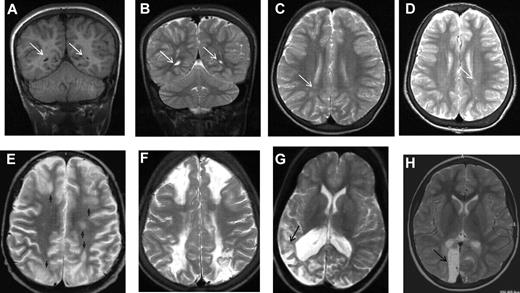

MRI in sickle cell disease. Coronal T1-weighted MRI (A,E) and axial T2-weighted MRI (B-D,F-H) in patients with homozygous SCA. (A-C) Normal MRI in a 19-year-old man with homozygous SCA. (D) Three years later, there is no change. (E-G) Silent infarction (arrows) in the frontal white matter and basal ganglia in a 15-year-old girl with cognitive problems affecting school performance but no acute neurologic presentation. (H) Three years later she has further infarcts with evidence of mild generalized atrophy and had a transient right hemiparesis as well as developing signs of a diplegia.

MRI in sickle cell disease. (A) Coronal T1-weighted MRI, (B) coronal T2-weighted MRI, and (C-H) axial T2-weighted MRI in patients with homozygous SCA. (A-C) Silent cerebral infarction (white arrows) in the parietal white matter in a 10-year-old girl with headache. (D) Three years later, there is progressive atrophy on MRI in the context of intermittent ataxia and squint. (E-H) Four cases associated with acute illness. (E) Silent cerebral infarction (black arrows) in the watershed regions between the anterior, middle, and posterior regions, including the deep white matter, in a patient who had previously had posterior reversible encephalopathy syndrome in the context of cyclosporine treatment for nephrotic syndrome. (F) Bilateral watershed infarction in a child who had seizures in the context of a facial infection. Motor examination was normal but his IQ was reduced by 30 points compared with premorbid testing. (G) Encephalomalacia after sagittal sinus thrombosis secondary to pneumococcal meningitis. (H) Occipital infarction after acute chest crisis. A homonymous visual field defect was detected after the infarct was noted on MRI.

In the first systematic study of SCI in adults with SCA, Vichinsky et al used a definition of a minimum of 5 mm signal hyperintensity in the T2-weighted image,9  but to be included, lesions also had to show corresponding hypointensity on the T1-weighted image (Figures 1E, 2A). Normal adults typically accumulate T2 hyperintensities as they age, but children do not. This more restrictive definition of SCI and the distinction from encephalomalacia and atrophy (Figures 1H, 2D-H) parallels the descriptions used in general populations of asymptomatic elderly adults with SCI.10

As part of the protocol for the observational CSSCD cohort, the leadership group added serial surveillance MRI scans of the brain of children beginning at 6 years of age. A total of 266 children with SCA hemoglobin SS (HbSS) completed both a MRI of the brain and a battery of age-appropriate tests of cognitive function. The average age at initial scan was 8.3 years with each child having at least 1 follow-up scan at a mean of 12.1 years of age. The mean interval between first and follow-up studies was ∼ 2 years. In this cohort, the prevalence of SCI at baseline was 21.2%.15  SCIs commonly differ in size and location compared with overt strokes. Whereas overt strokes are typically located in both cortex and deep white matter,16  SCI in the CSSCD typically occurred in the deep white matter of the frontal (81%; Figure 1E-F) or parietal (45%) lobes (Figure 2A-D), followed in frequency by the basal ganglia (Figure 1G-H) or thalamus (16%) and the temporal lobes (9%).15  Similar observations were reported for an unselected cohort of 132 children with SCA in Créteil, France undergoing brain MRI as part of routine medical care2  and in other studies.4,5,17,18  SCI in SCA are typically smaller in size compared with overt strokes. In the CSSCD participants, 83% of the children with overt strokes, but only 16% of those with SCI, had lesions that were at least 1.5 cm.15